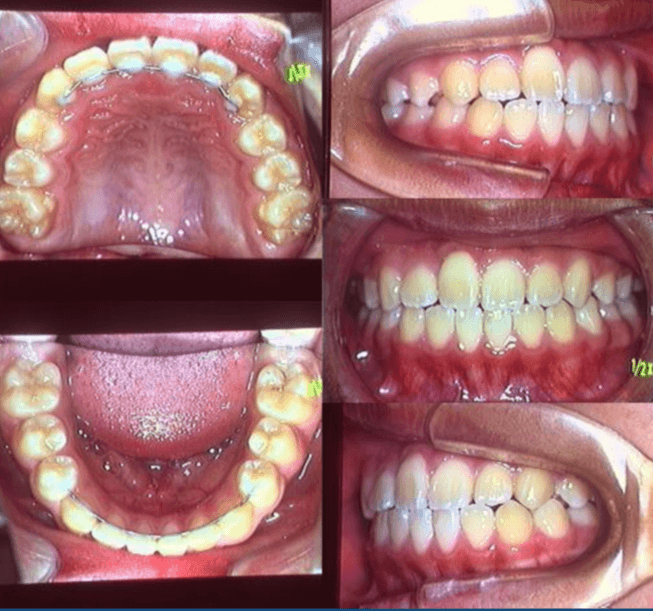

| 年齢・性別 | 11歳1ヶ月の女性 |

|---|---|

| 主訴 | 口元の突出感と歯並びが気になり、将来的な咬合状態を整える目的で来院された患者様です。 |

| 治療期間・回数 | 2年6ヶ月・25回 |

| 費用 | 720,000円 |